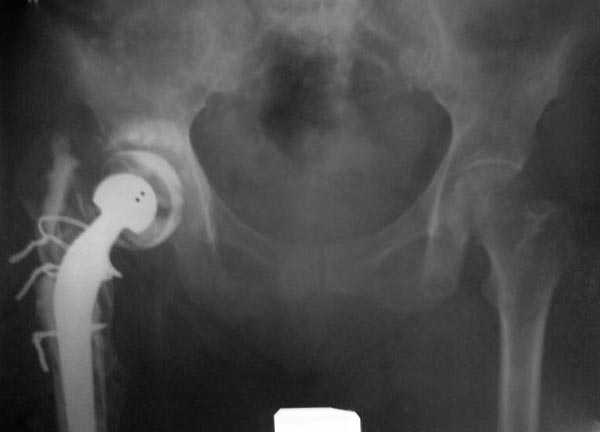

Если снимок справа по хронологии последний, то в тазобедренном сустава наступил анкилоз. Это хороший плюс костной ткани для постановки чашки эндопротеза, но отсутствие сохранения биомеханической оси бедренной кости ставит под вопрос благоприятный вариант усановки ножки эндопротеза.... Учитывая выполненную остеотомию, не считаю выполнение скелетного вытяжения лишенным смысла, для восстановления оси конечности с последующим, возможно, индивидуальным эндопротезированием.

Очень признателен Вам за ответ, но позвольте мне не согласиться с Вами. Я бы пока не делал вывод о анкилозировании тазобедренного сустава. На рентгеновских снимках, да и по данным компьютерной томографии (а этот метод один из самых современных и информативных), хорошо прослеживается постоянной ширины щель между головкой бедренной кости и вертлужной впадины. Кроме того, несложно увидеть разницу "шеечно-диафизарного угла" до и после выполнения тракции в аппарате. Хотя, Алексей, даже если я и прав, это не сильно облегчает нашу задачу.

Вот снимки по свежей ситуации, парень 19 лет, длинный оскольчатый перелом бедра от шейки до в-с/3. давно уже ходит на своих ногах.

Представленные Вами рентгенограммы действительно являются примером качественной фиксации спице-стержневым аппаратом. Они, как ни что другое, многое иллюстрируют.

Компоновку данного аппарата, в котором дистальный отломок фиксирован лишь на дистальном уровне, а проксимальный вообще сам по себе никак, только через бывший сустав, назвать стабильной никак нельзя. Нет стабильности - нет нормального заживления, но есть осложнения, надеюсь, это-то можно экстраполировать на вашего больного?